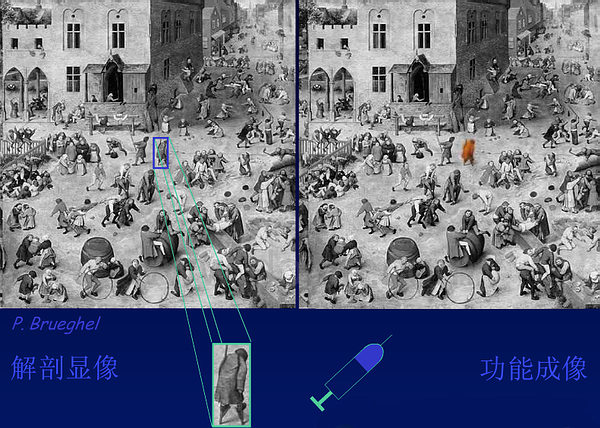

Positron Emission-computed Tomography(正电子发射计算机断层扫描),阐述了FDGPET/CT根本原理是上面提到利用正电子β+来成像得到PET图像,在技术层面上与CT图像进行融合,在功能成像的基础上获得准确的解剖定位,告别“Unclear Medicine”时代。